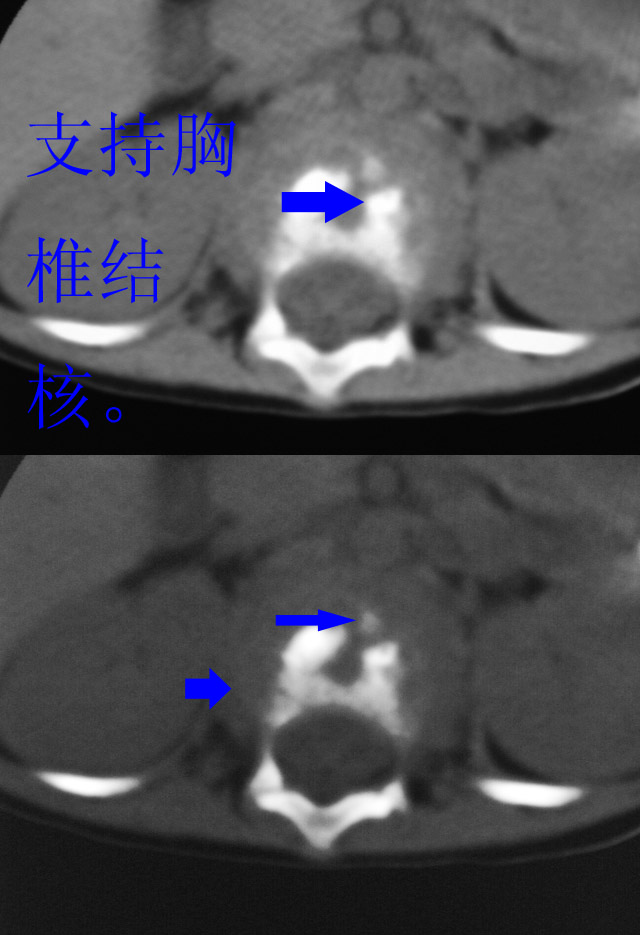

病人男性,一岁半.外伤后腰痛两天.外院x片报腰1压缩性骨折.追问病史,一年前曾有过持续高烧史.血常规及血沉结果未出.

结核,建议msct

椎体周围见类软组织密度影,椎体见虫蚀样破坏,考虑tb.性。

椎体骨质破坏,椎体周围见软组织密度影.椎体结核

椎体破坏明显,周围软组织肿胀,椎间盘未见明显受累.结核

椎体破坏明显,周围软组织肿胀,椎间盘未见明显受累.考虑结核

椎体结核合并冷脓肿形成。

椎体破坏明显,周围软组织肿胀,椎间盘未见明显受累.考虑椎体结核合并冷脓肿形成。

体破坏明显,周围软组织肿胀,椎间盘未见明显受累.考虑椎体结核合并冷脓肿形成.注意排除嗜酸性肉芽肿